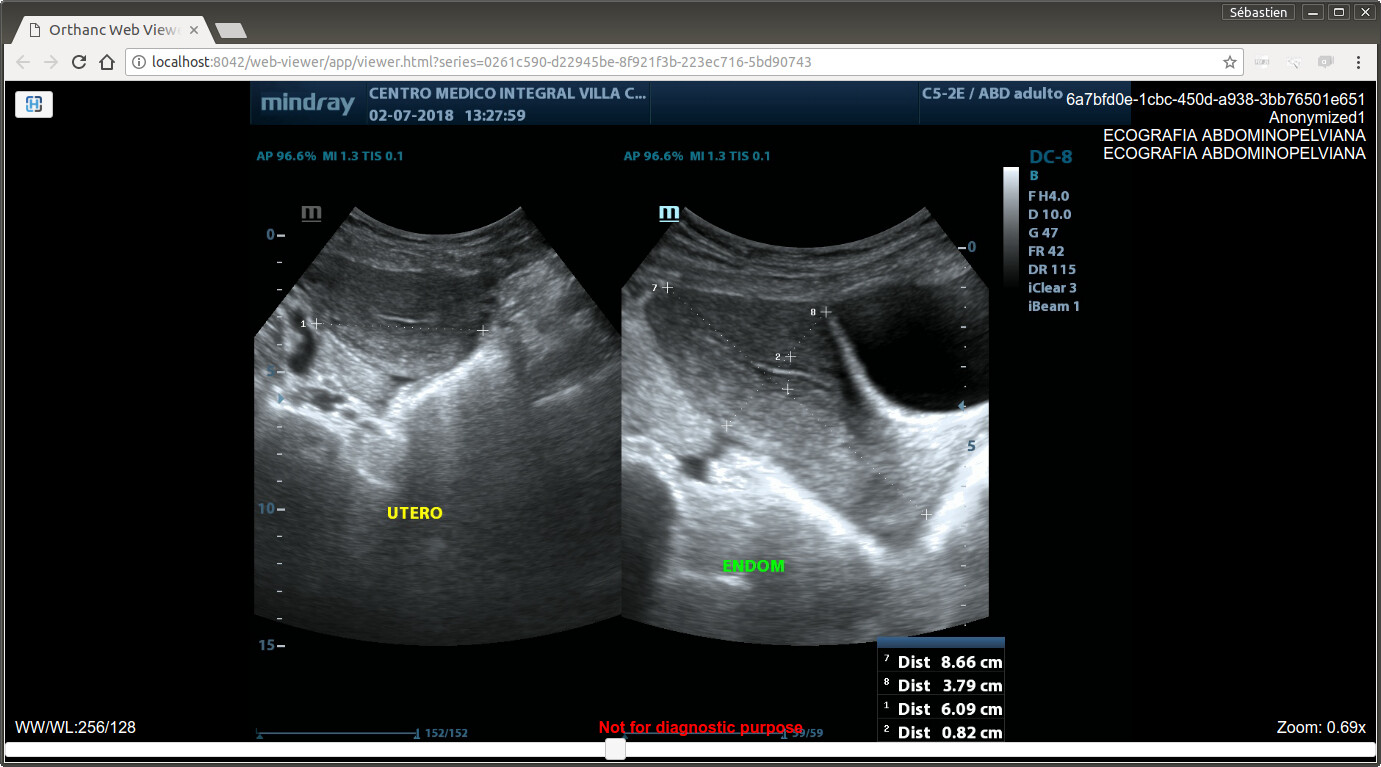

Dear Daniel,

I have tested your image using the Orthanc basic Web viewer, and it works properly on your image (see attachment).

Until the Osimis Web viewer is fixed, you are thus kindly invited to use the Orthanc basic Web viewer:

https://www.orthanc-server.com/static.php?page=web-viewer